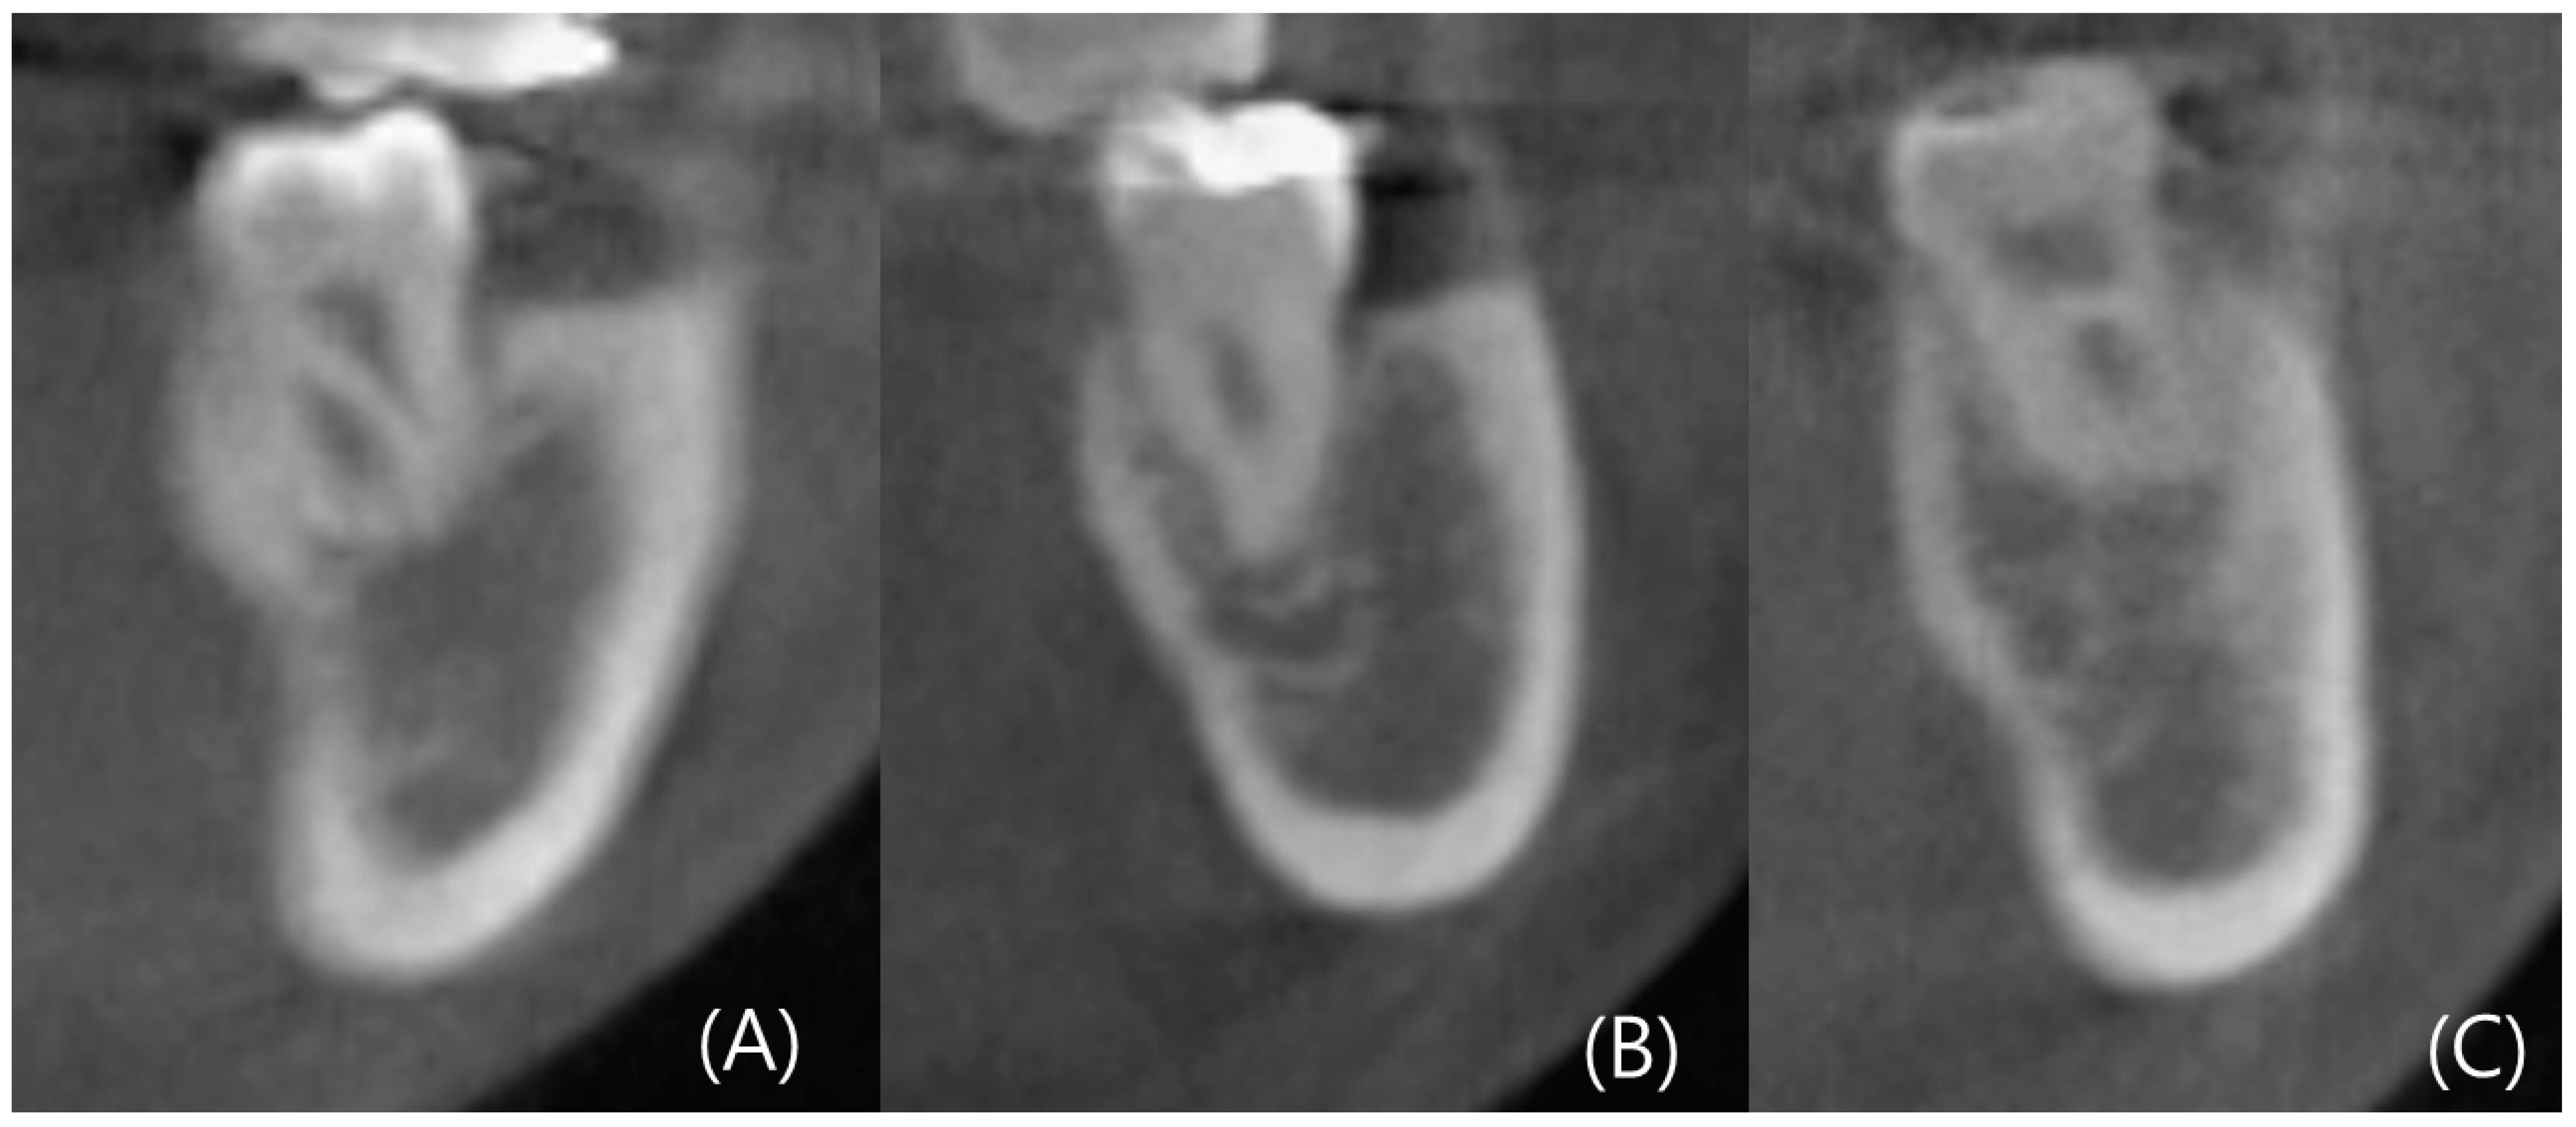

CBCT images were reconstructed into cross-sections using Invivo 6 (Anatomage, Santa Clara, CA, USA). Analysis of the left and right mandibular first and second molars was conducted in 96 patients, resulting in the analysis of 384 cross-sectional images. Landmarks such as the alveolar crest, inferior alveolar nerve canal, and mandibular lingual concavity were used for analysis. Line A was drawn two millimeters (mm) above the superior border of the inferior alveolar nerve. Line A served as the reference for the ridge, and the width of the ridge at the level of Line A was measured as Wb. Additionally, the width of the ridge, which was two mm below the alveolar crest, was measured as Wc. Wb and Wc were used to determine the ridge shape. The height between the baselines of Wb and Wc was measured as Vcb. According to Chan et al.’s criteria, the lingual concavity of the mandible was classified as U, C, or P type. The ridge of the C type was wider than Wb, while the ridge of the U type was wider than Wc. The ridge of the P type had similar widths for Wc and Wb.

The degree of concavity for the U type was separately evaluated. The deepest point of the inner concavity was marked as the A point, and a horizontal line passing through the A point was referred to as Line B. The highest point of the inner concavity was marked as the P point, and the line connecting the A point and P point was termed Line C. The angle between Lines B and C was measured as the concavity angle. The line connecting the A and P points was labeled as Line 1, and its length was measured as the concavity length. The depth of the concavity was determined by drawing a perpendicular line through the deepest point of the concavity, and the length of this perpendicular line represented the depth (Figure 2 and Figure 3) [13].

Figure 2.

Type of anatomical mandibular ridge (A) type U (B) type P (C) type C.

Figure 3.

Demonstration of dimensional measurements of alveolar ridges. The red point is the inferior alveolar nerve (IAN) canal. (A) Dimensional measurement (B) Degree of lingual concavity—Angle (C) Degree of lingual concavity—Length, Depth.